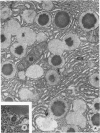

The pathogenesis of a spontaneously occurring exocrine pancreatic insufficiency (EPI) syndrome in CBA/J mice was studied at the ultrastructural level. Initial cytologic manifestations of this syndrome are seen as a progressive digestion of the zymogen granules, beginning at the periphery and proceeding toward the granule interior. Granule membrane breakdown, fusion of neighboring granules, and a release of zymogen contents into the cytoplasm are frequently observed in later stages; in some cases the entire granule contents appear digested before membrane breakdown is observed. In either case, pathologic changes are subsequently observed in mitochondria and rough endoplasmic reticulum. Remnants of lysed cells are then engulfed by invading macrophages, and infiltration by fat cells is observed. Secretory ducts and islets of Langerhans show no pathologic changes even after total autolysis of the exocrine pancreas. Morphologic evidence showing zymogen granule destabilization, coupled with biochemical evidence presented in an accompanying paper, indicate that intracellular autodigestion is the mechanism of exocrine cell death.